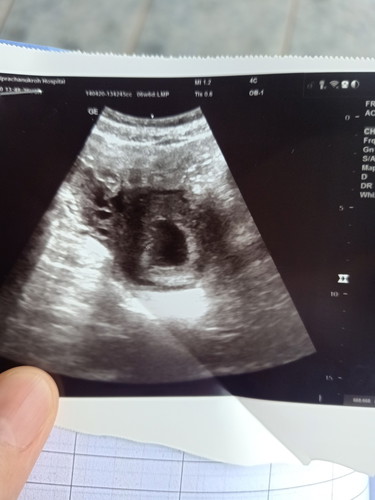

ตอนนี้ตั้งครรภ์ได้6w5dไปซาวมาเจอแต่ถุงตั้งครรถ์ไม่เจอตัวเด็กกังวลมากเลยคะ.แม่ๆเจอเด็กตอนกี่วีคคะ?

?หมอนัดอีกที27นี้คะ